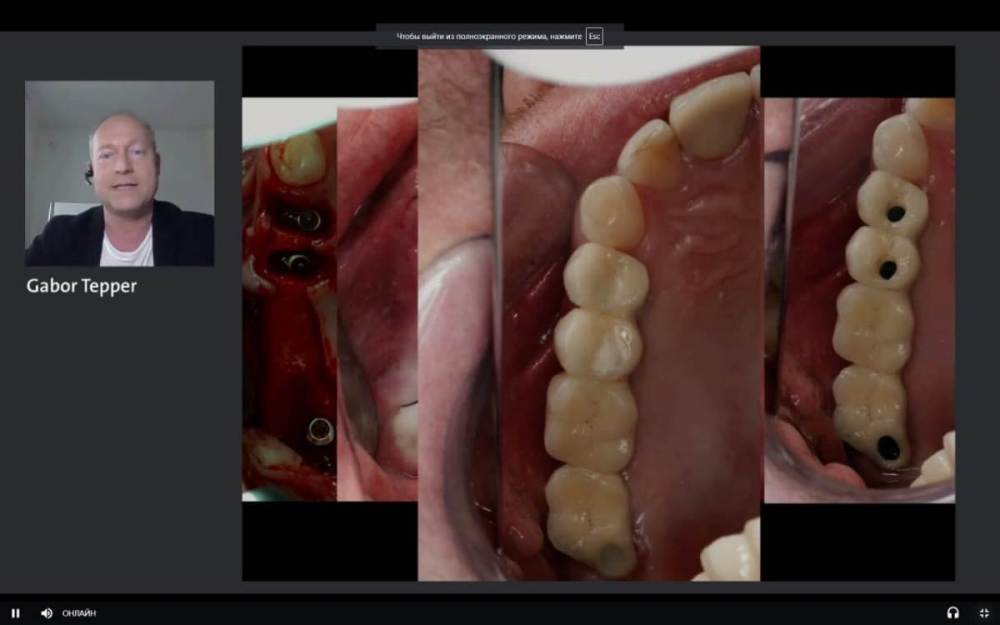

It'sGeorgy Опубликовано 10 мая, 2021 Поделиться Опубликовано 10 мая, 2021 (изменено) Если есть фото и снимок после протезирования, добавьте пожалуйста. Правильно ли я понимаю, что у дистального имплантата мультиюнитом выход шахты будет как раз посередине 1.7? Что думаете о таком концепте? (взял со Штраумянского недавнего онлайн-форума) Изменено 10 мая, 2021 пользователем It'sGeorgy Ссылка на комментарий

Карен Аванесов Опубликовано 10 мая, 2021 Автор Поделиться Опубликовано 10 мая, 2021 17 минут назад, It'sGeorgy сказал: Если есть фото и снимок после протезирования, добавьте пожалуйста. Правильно ли я понимаю, что у дистального имплантата мультиюнитом выход шахты будет как раз посередине 1.7? Что думаете о таком концепте? (взял со Штраумянского недавнего онлайн-форума) Фото покажу позже. Да, возможно так и будет. Очень здорово что Вы смотрите такие онлайн-форумы, наверно поучительно. Моей работе на слайде 7 лет, хирургия и ортопедия моя, зуботехническая работа такая как есть, фиксация цементная, на дистальном имплантате индивидуальный титановый абатмент, тем не менее нет каких либо проблем. Близкое расположение имплантатов, в данном случае рентгенологический артефакт. Пациентке было с чем сравнивать ощущения, слева делал открытый синуслифтинг, гуманный подход он лучше для пациента и оператора, на мой взгляд. 2 1 2 Ссылка на комментарий